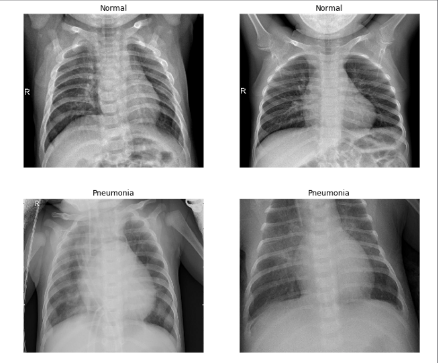

Another drawback for the early diagnosis of pneumonia is the human-dependent detection. Expert radiologists need to have sufficiently trained eyes in order to be able to differentiate between the heterogeneous color distribution of air while flowing in the lungs. This may be seen in different colors on the x-ray image taken, yet not be the dense pneumonia fluid. Thus, it’s highly significant for a radiologist to be able to tell whether if the white spots on the x-ray film actually correspond to the fluid itself. As a result of the error margin of the human eye, there are many cases where the radiologists fail to make the correct diagnosis. In both cases, whether if it’s a false positive or false negative diagnosis, it has substantial impacts on the human body. Therefore, computational methods in the diagnosis step of the disease are reliable in terms of consistency. In fig 1, different images with and without pneumonia can be seen ([2]). The imperceptibility of the healthy versus the pneumonia images can also be witnessed, which portrays the need of well-trained eyes in order to be able to differentiate.

Refer to caption

Figure 1: X-ray Images with and without Pneumonia